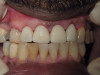

Cosmetic